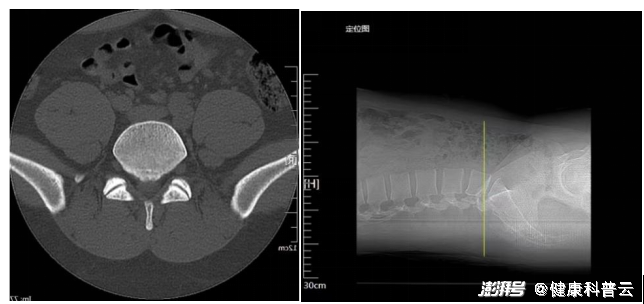

腰椎三维CT

腰椎MRI

入院后检查提示腰5/骶1椎间盘向右后脱出,脊髓神经受压明显,患者存在腰5/骶1椎间盘向右后脱出并椎管狭窄,需要手术扩大狭窄的椎管并摘除突出的腰椎间组织解除神经受压,适合采用UBE技术为患者进行手术治疗。术前制定了严密的手术治疗方案,并与患者及家属充分、细致沟通。手术中分别在患者腰后右侧开两个小孔探入病灶。一个通道用于持续冲洗和手术视野的内镜暴露,另一个通道是用于手术操作。通过内镜传输到屏幕上放大数倍的医学影像,可以清晰地查看到组织内部结构。